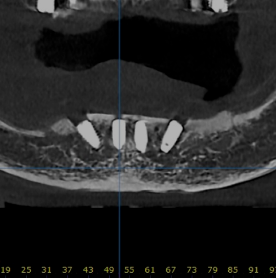

디지털 풀아치

할까? 말까?

틀니가 잘 빠지고 불편해서 고민이세요?

디지털 풀아치가 해결해 드립니다